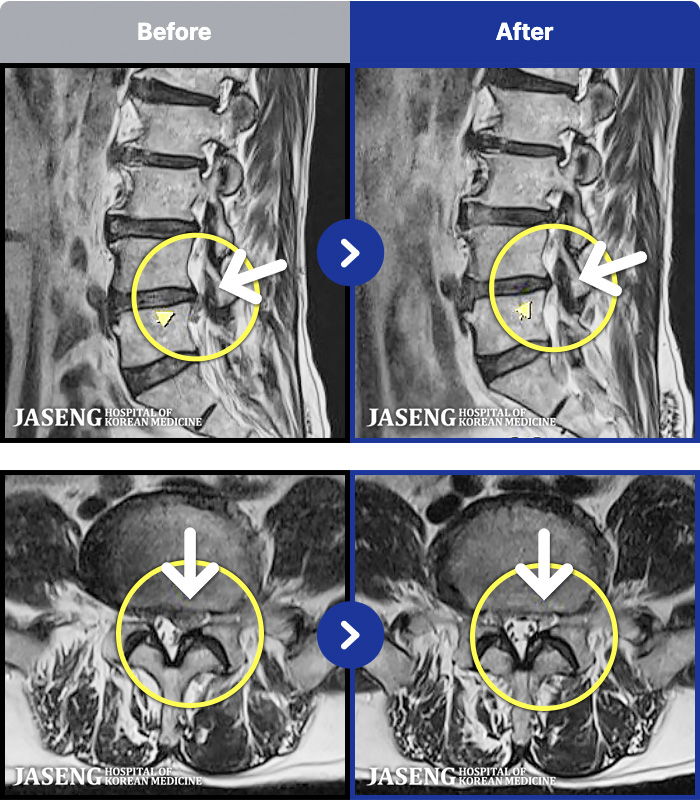

97 MRI ũ ʸ Ȯϼ.

ȯںп Ǹ ǿ ԿǾ, ο ġ ۿ Ƿ ġḦ Ͻñ ٶϴ.